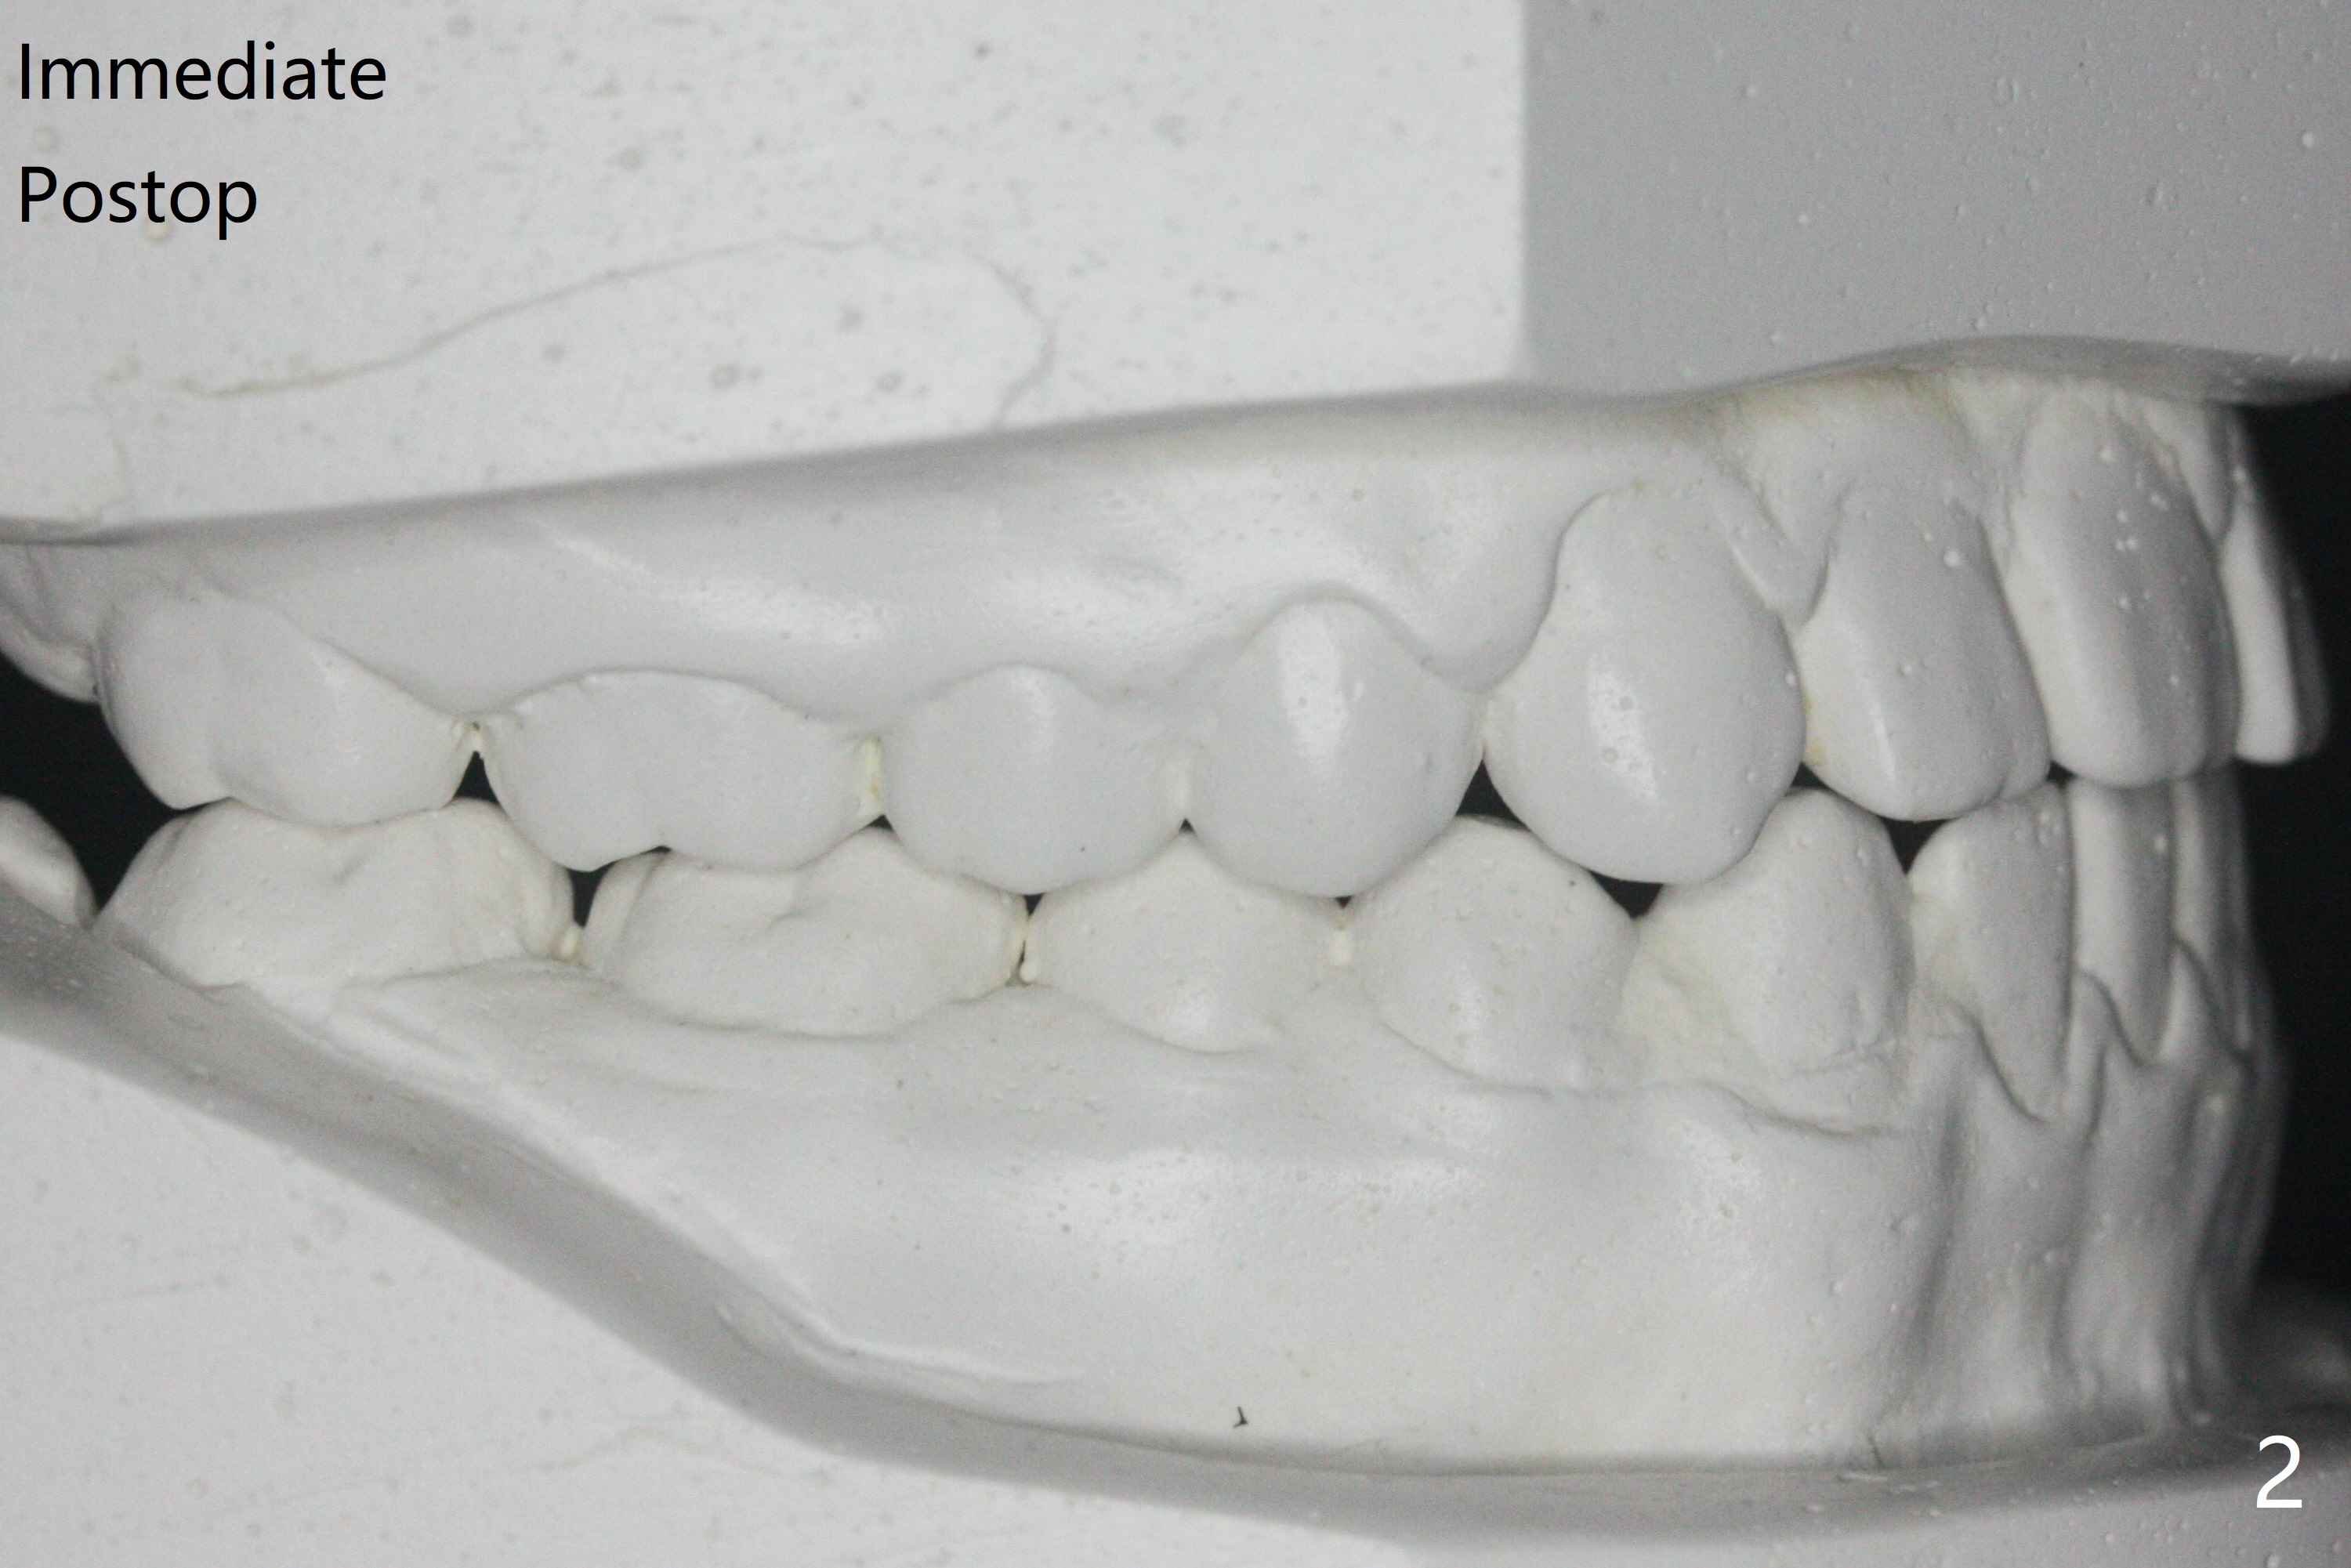

15岁男完成矫正1年9月,右侧后牙咬合理想(图二),上中切牙长轴改善,侧切牙torque不够完善(图四),左侧后牙咬合二类𬌗(图六,需要牵引),磨牙缝隙大(图八,十),造成食物堵塞,以后尽量避免使用磨牙bands,尤其是成人。